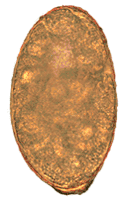

Morphology

Eggs of N. salmincola are light brown, ovoid, and operculate at one end, with a small blunt projection at the other end. They measure 0.087 mm to 0.097 mm by 0.038 mm to 0.055 mm.[12] There are normally 5 to 16 eggs in the uterus, and their heaviness allows them to sink rapidly in water.[12]

N. salmincola is a digenic trematode, which means that it is an unsegmented worm that is flattened dorsoventrally. Adult worms alternate shape from "a sphere to a long blunt rod".[12] The worms are 0.8 to 1.1mm long and 0.3 to 0.5 mm wide and are hermaphroditic, having both male and female reproductive organs in the same organism. The two large oval testes are 0.2 to 0.3 mm long and the round ovary is 0.07 to 0.11 mm in diameter.[11] N. salmincola has a prominent cirrus pouch, or hollow organ surrounding the male copulatory organ, but no seminal vesicle. True to its character as a trematode, it has an oral sucker 0.15 to 0.18 mm in diameter, and a ventral sucker 0.12 to 0.13 mm in diameter.[11] The oral and ventral suckers are used to grasp and crawl actively about the intestinal tissue of its host, though the worm leaves no extensive mechanical damage.[12]